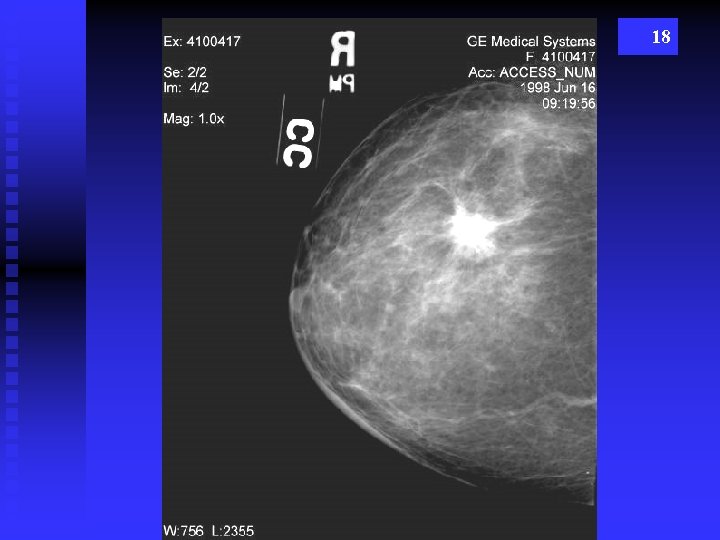

18